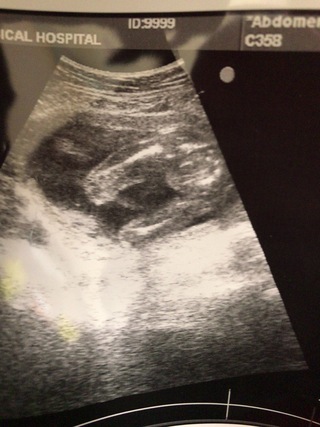

男の子か女の子かわかる人いますか 男の子か女の子かわかる人いま 赤ちゃん 教えて Goo

19週のエコーなんですが 男の子か女の子か分かりますか 見にく Yahoo 知恵袋

性別わかりますか 20週に入りました このエコー写真で男の子か女の子かわか Yahoo 知恵袋

こんにちは ベビーナブについて教えて頂きたいです こちらは12週のエコー Yahoo 知恵袋

妊娠7ヶ月です おまたの下から撮ったエコーです 男の子か女の子か 妊娠 教えて Goo